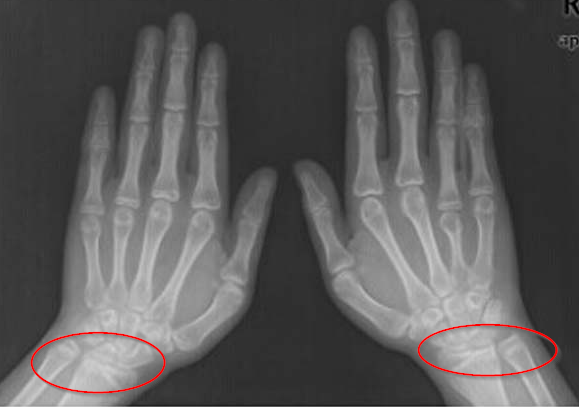

腕关节:两个自由度。通过将手掌平放在桌子上,我们实际上可以在平面上或垂直于桌子上下旋转它们。手腕上的关节特别多,用红线标出。